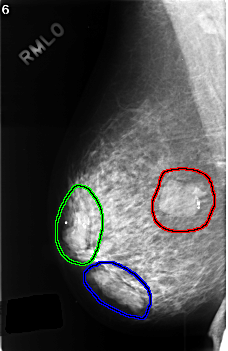

C_0384_1.RIGHT_MLO

RIGHT_MLO LINES 4552 PIXELS_PER_LINE 2960 BITS_PER_PIXEL 12 RESOLUTION 50 OVERLAY

FILE: C_0384_1.RIGHT_MLO.OVERLAY

TOTAL_ABNORMALITIES 3

ABNORMALITY 1

LESION_TYPE MASS SHAPE LOBULATED MARGINS CIRCUMSCRIBED

ASSESSMENT 3

SUBTLETY 5

PATHOLOGY BENIGN

ABNORMALITY 2

LESION_TYPE MASS SHAPE OVAL MARGINS CIRCUMSCRIBED

ABNORMALITY 3